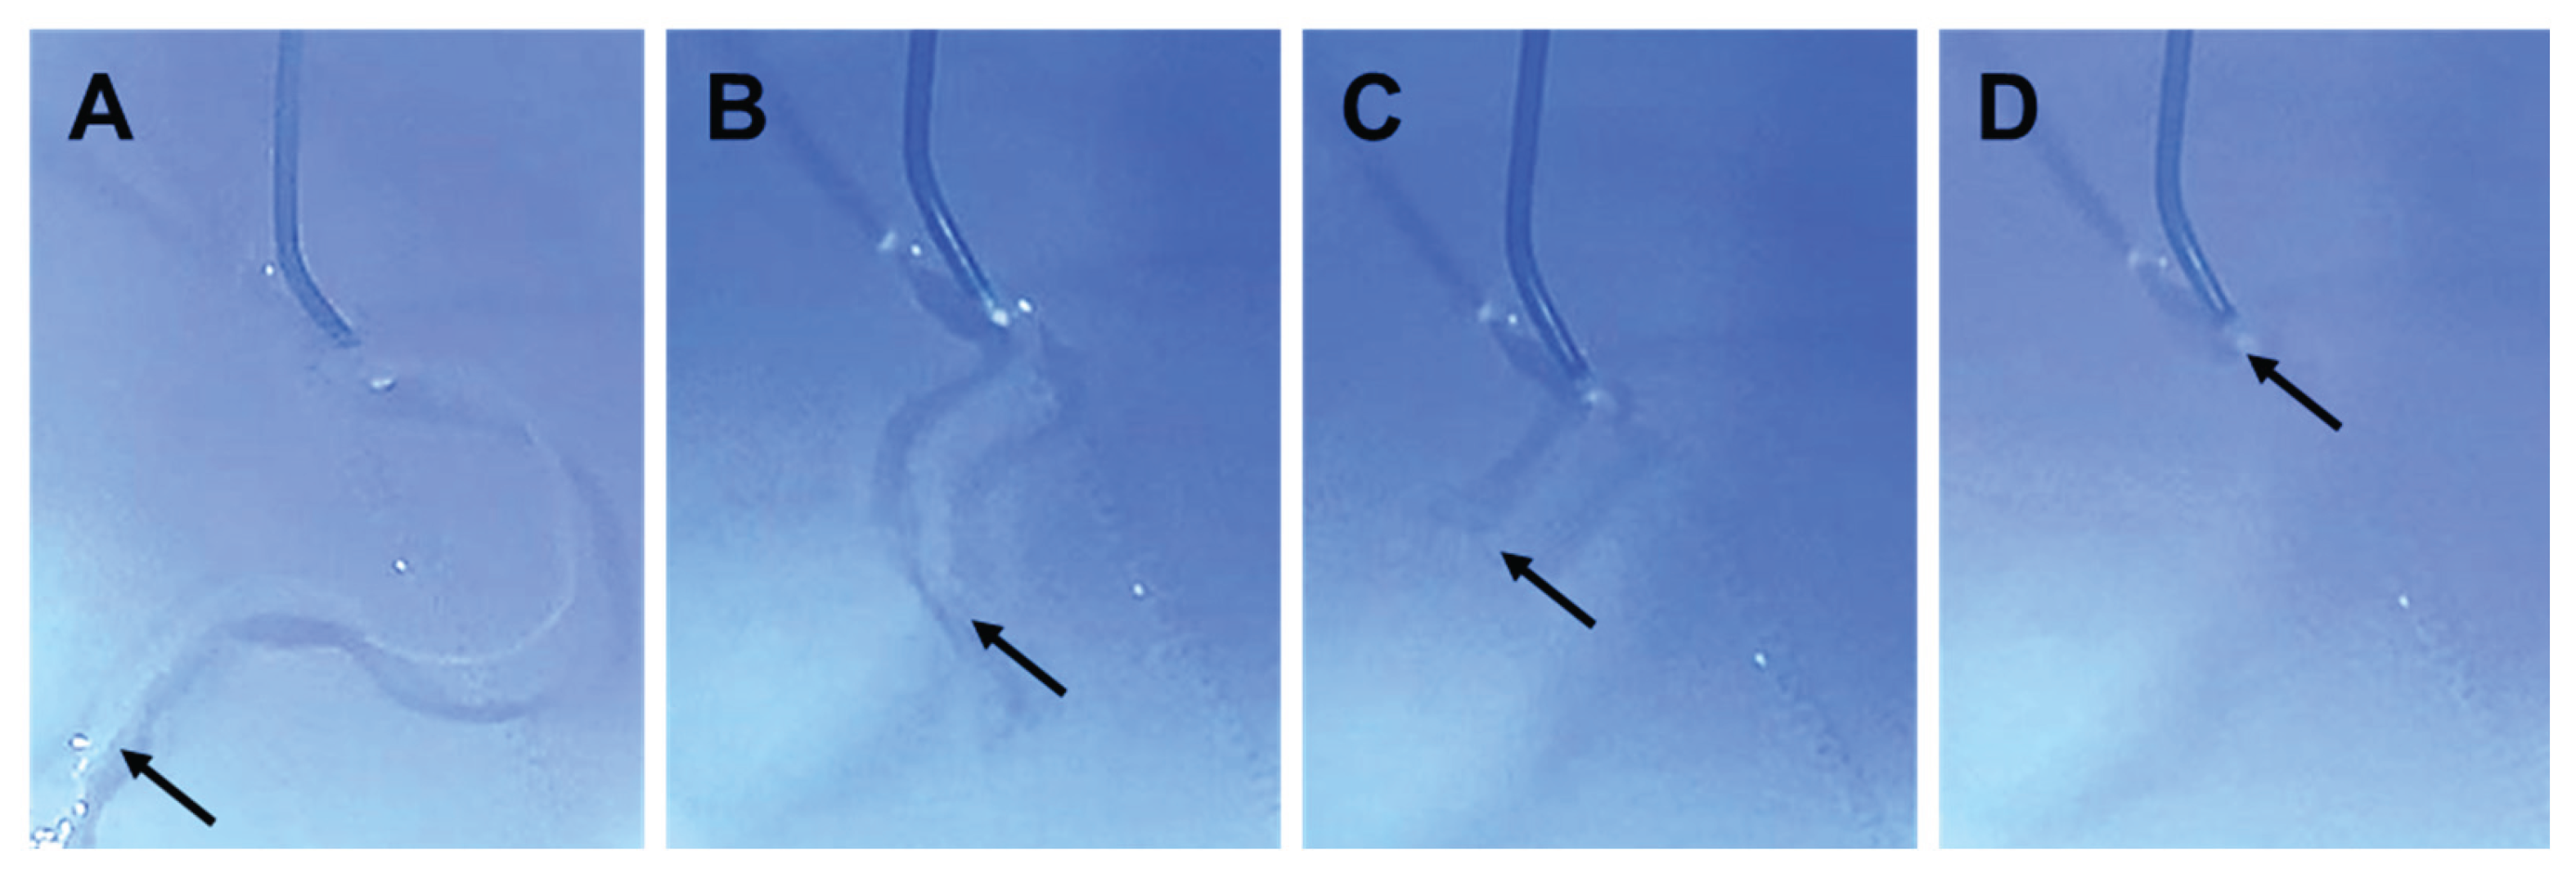

3.2. HMSC Fiber Manipulation

When negative pressure was applied to the catheter, the HMSC fiber was smoothly aspirated from the catheter tip without structural collapse and was completely accommodated within the catheter lumen (Figure 5A and Supplementary Movie S2). The HMSC fiber remained intact during aspiration and was stored completely inside the catheter along its entire length (Figure 5B–5D).

Sequential images showing the process of loading an HMSC fiber into a catheter lumen. The HMSC fiber was aligned at the catheter tip (A), subsequently accommodated within the catheter lumen (B, C), and fully contained inside the catheter prior to delivery (D).